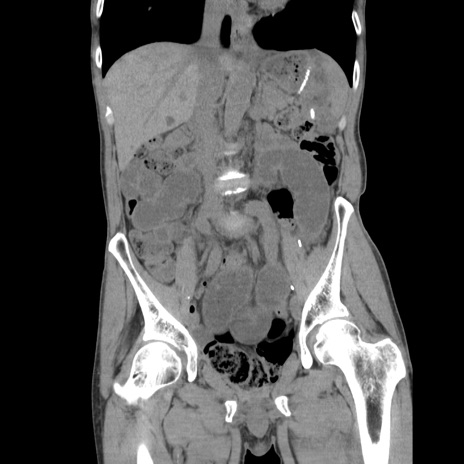

症例11(冠状断像)

【症例】 60歳代男性

【主訴】 下腹部痛

【現病歴】 本日夜中より下腹部痛の症状認め、受診。

【既往歴】 膀胱癌(膀胱全摘+尿管皮膚瘻術) 、胃癌術後

【身体所見】 BT 35.3℃、PR 58/min、BP 136/98mHg、腹部平坦、軟、腸蠕動音±、ストマ留置あり、左上腹部~正中部に圧痛あり、反跳痛なし。

【データ】WBC 5100、CRP0.01